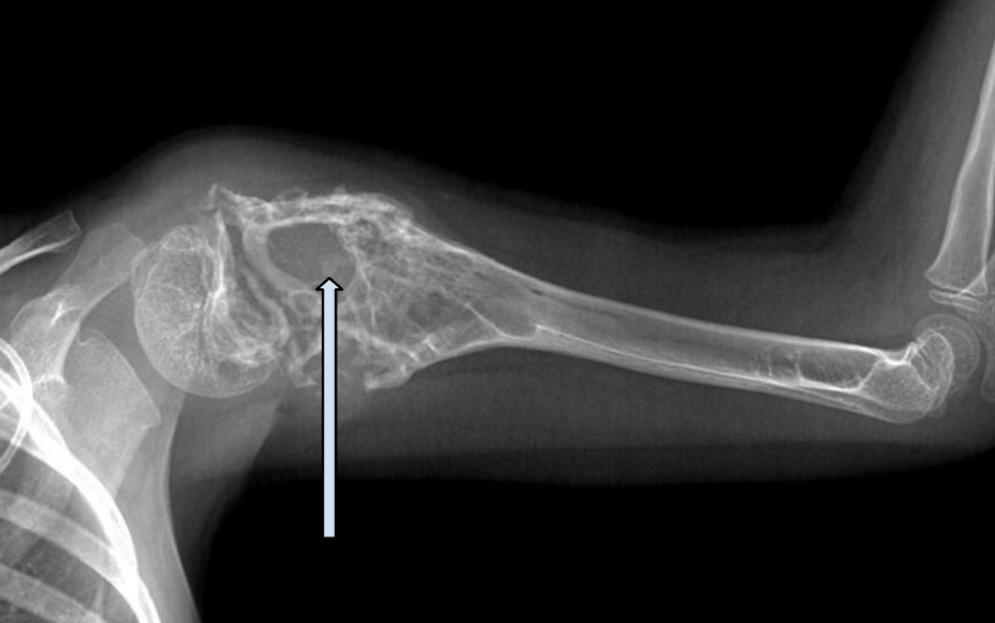

Выше — множественные очаги деструкции (разрушения) плечевой кости; опухоль разрушает нормальную костную ткань, кость становится менее плотная, тем самым повышается риск патологического перелома.

Основные симптомы – боль и отек в месте, где находится первичная опухоль. У большинства пациентов боль длится несколько месяцев — в среднем 3-4, часто возникает после травмы. Со временем она может усиливаться или ослабевать. Из-за разрушения опухолью костной ткани могут происходить патологические переломы.

При значительном опухолевом поражении может произойти патологический перелом кости — при незначительной травме или минимальной нагрузке нарушается ее целостность.